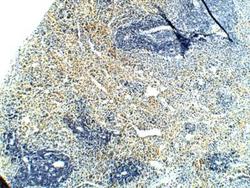

Supportive validation

- Submitted by

- Novus Biologicals (provider)

- Main image

- Experimental details

- Immunohistochemistry-Paraffin: PAR2 Antibody [NBP2-11250] - 1:100 dilution in IHC blocking buffer. DAB (brown staining and Hematoxlyn QS (blue) counsterstain. FFPE section